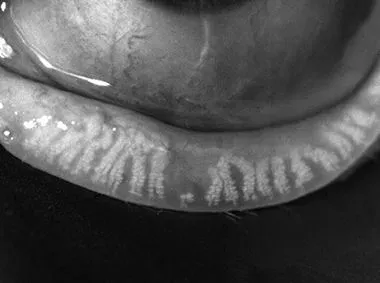

Dynamic Meibomian Imaging

MEIBOMIAN GLANDS IN HIGH DEFINITION1

Adaptive Transillumination

Changes to the light intensity across the surface of the illuminator compensate for the lid thickness variations between patients.

Dual-Mode DMI

Dynamic Illumination offers an enhanced view of meibomian gland structure.

Dynamic Meibomian Gland Imaging

Utilizes advanced illumination technology to capture high-definition images.

• High-definition imaging with Dynamic Meibomian Imaging1